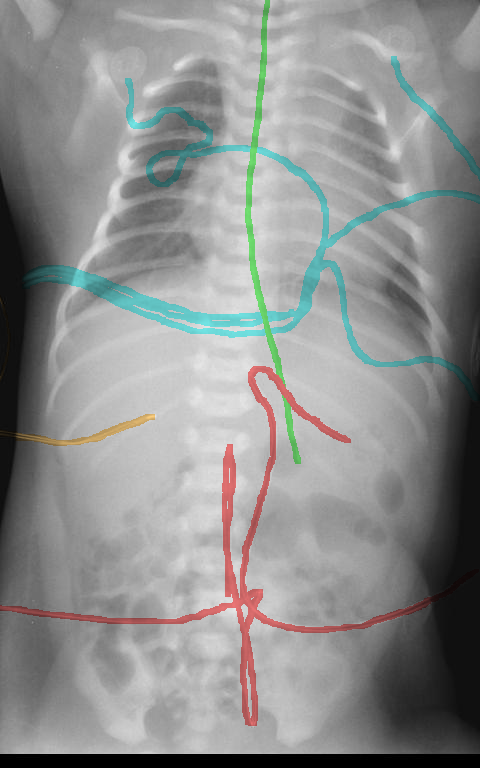

Automated catheter detection is a challenging task. Although most catheters have a radiopaque strip to facilitate detection, the strip may become less apparent depending on the projection angle. Catheters maybe confused by other similar linear structures like ECG leads and anatomy including ribs. Additionally, portions of catheters can be occluded by anatomical structures given that radiographs are a 2D projection of a 3D structure. For example, when a NGT is placed within the oesophagus, the catheter itself becomes less apparent due to the high density of the adjacent vertebrae. Finally, the number and type of catheters that could possibly appear in pediatric X-rays are unknown a priori. The catheters may be intertwined with each other thus making simple line tracing methods fail. Figure 1 gives three sample pediatric X-ray images with some common catheters highlighted in different colors.

To alleviate this annotation problem in catheter detection, we proposed to use X-ray images with simulated catheters by exploiting the fact that catheters are essentially tubular objects with various cross sectional profiles. To be more specific, a synthetic 2D projection of a catheter is generated by first simulating a horizontal catheter profile and then using it as a brush tip to draw along a B-spline path. This generated catheter is then composited with an X-ray image serving as the training data. Another contribution of this work is a segmentation network that can inherently take into account multi-scale information. This network adopts a UNet-style form and contains a recurrent module that can process inputs with increasing scales111Our code is available at https://github.com/xinario/catheter_detection.git.. We have empirically shown that by iterating through the scale space of the input image, higher recall is achieved as compared to using a single scale. Details about the methods are discussed in Section 3. Three sample detection results are shown in Figure 1.

The test dataset is collected locally and only contains frontal chest-abdominal X-rays from patients < 4 weeks old. This is the most common radiograph obtained to confirm placement of catheters such as UACs and UVCs in neonates. Currently, the test set has 35 fully labeled images with different catheter types with sample images previously shown in Figure 1. All the annotated catheters (lines excluding ECG leads) are treated as the same class in the detection.